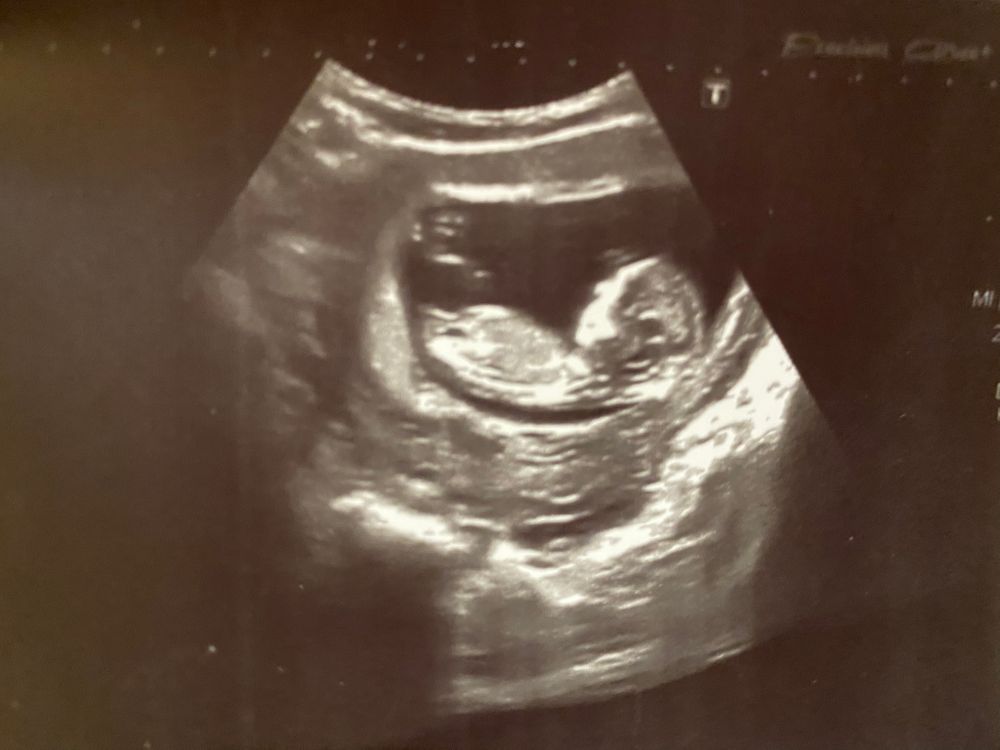

Первое плановое УЗИ

Это девочка 🥰🥰🥰

Ирина Матвеева скоро стану мамой доченьки, Будем ждать второе плановое узи 🙏🏻

На девочку похоже 🥰

Я тоже по фото вижу девочку, у меня так же было) а у кого узи делали?)

Лапа какая)) Мне кажется, я вижу девчушку, как и у себя 😃

Нарушение кровотока в 23 недели Первый скрининг позади.